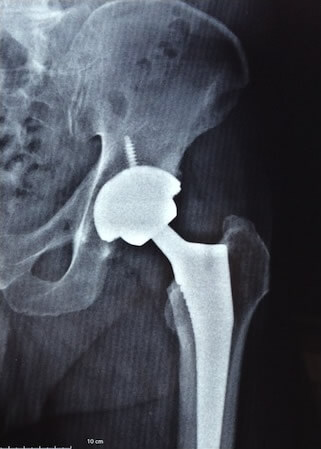

Fig. 3 - Exemplo de radiografia com prótese cimentada

Fig. 7 - Exemplo de raio-x pós-operatório de prótese não cimentada

Fig. 8 - Duas próteses híbridas, à direita o acetábulo com parafusos

Obs.: Os exemplos de radiografias apresentados acima são de pacientes operados por mim e publicados com seu consentimento, preservando sua identidade.